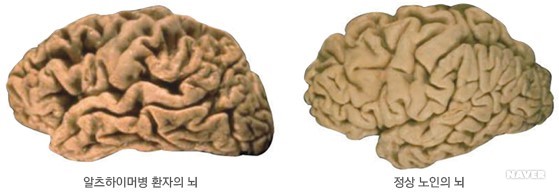

현미경으로 알츠하이머병 환자의 뇌 조직을 검사하였을 때 특징적인 병변인 신경반(neuritic plaque)과 신경섬유다발(neurofibrillary tangle) 등이 관찰되고, 육안 관찰 시에는 신경세포 소실로 인해 전반적 뇌 위축 소견이 보인다. 이러한 뇌 병리 소견은 질병 초기에는 주로 기억력을 담당하는 주요 뇌 부위인 해마와 내후각뇌피질 부위에 국한되어 나타나지만 점차 두정엽, 전두엽 등을 거쳐 뇌 전체로 퍼져나간다.

알츠하이머병 노인과 정상 노인의 뇌 모습